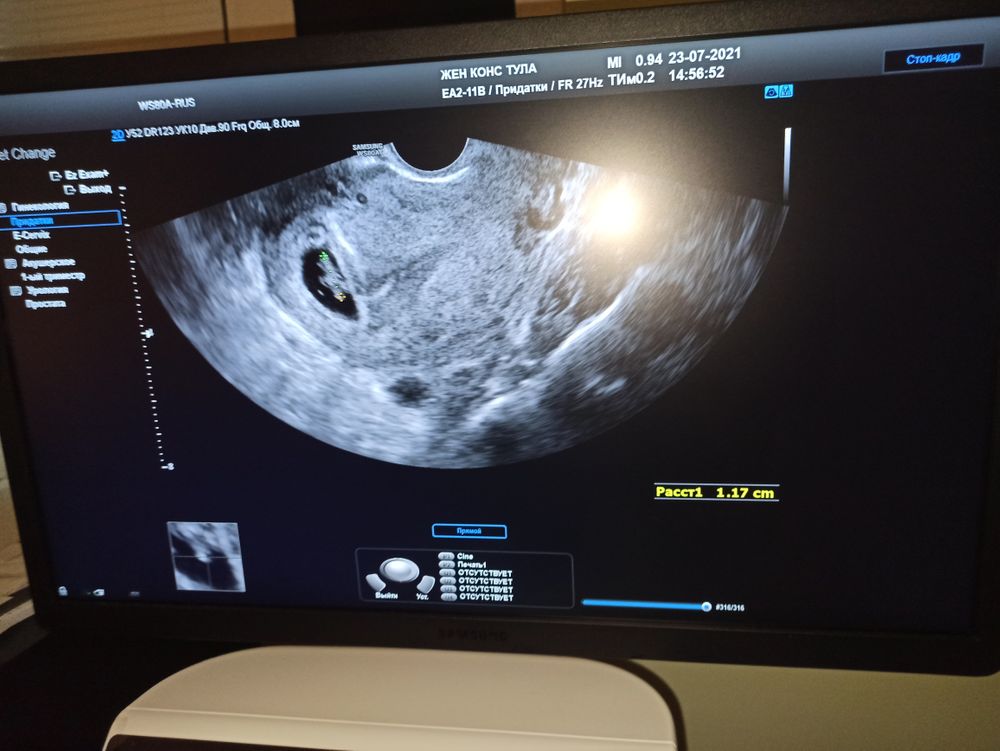

УЗИ трансвагинальное, срок 7,3 н

Мне тоже можете посмотреть кто разбирается,

узи обычное наружное, заранее благодарю😚😍